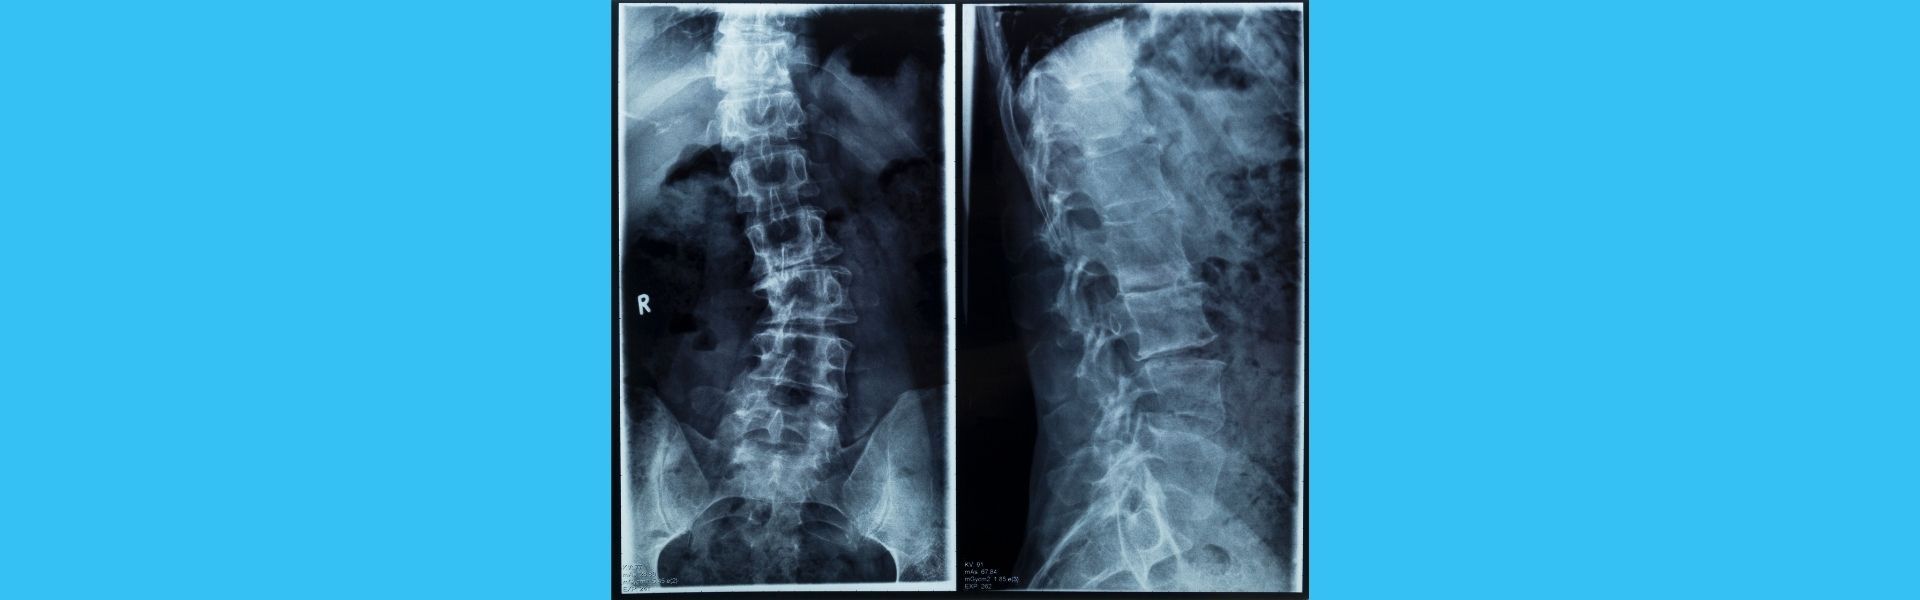

Fully Endoscopic Lumbar Hernia Surgery

A lumbar hernia when the discs between

the vertebrae in the lower back are damaged

and press on the spinal cord or nerve roots.